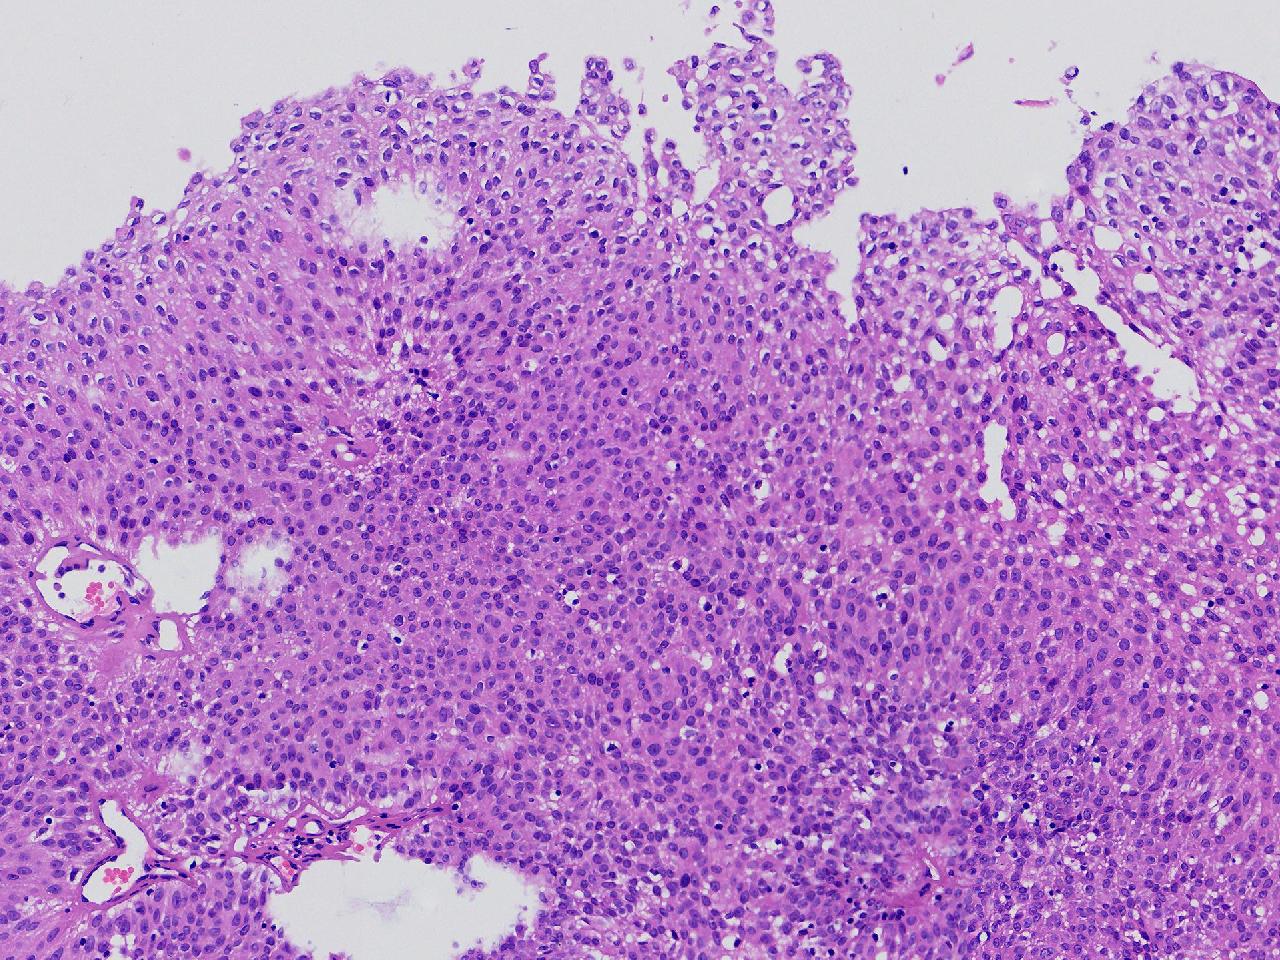

男,79岁,膀胱肿物。

膀胱肿物

灰白色不整形软组织多块,2X1X1厘米。

考虑:乳头状尿路上皮癌

乳头状尿路上皮癌,低级别。

这几张图片上没有看到明确的浸润。